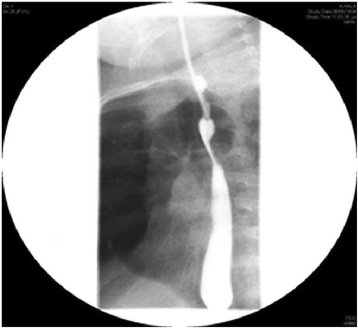

Case presentation: Here, we describe a 1-year-old Saudi female child with respiratory distress at birth. The child then had recurrent lower respiratory tract infections, bilateral lung emphysema with basal atelectasis, bronchospasm, pulmonary artery hypertension, and oxygen and mechanical ventilation dependency. Molecular testing showed a new pathogenic variant of one copy of c.3153dupC in exon 21 in the FLNA gene.